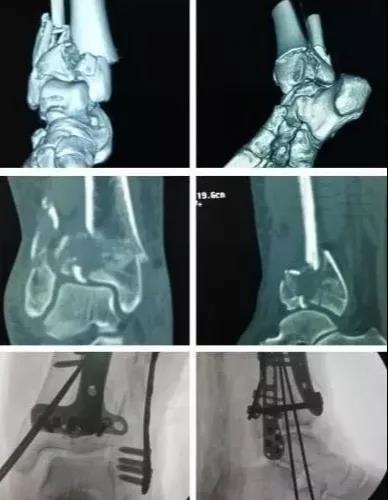

7)胫骨远端(pilon,踝部)

- pilon骨折,高能损伤,6-8h肿胀未形成,可以急诊做,手术时间<3小时。

- 10-14天,分步延期手术策略。

- 踝部骨折手术时机同样取决于皮肤条件。